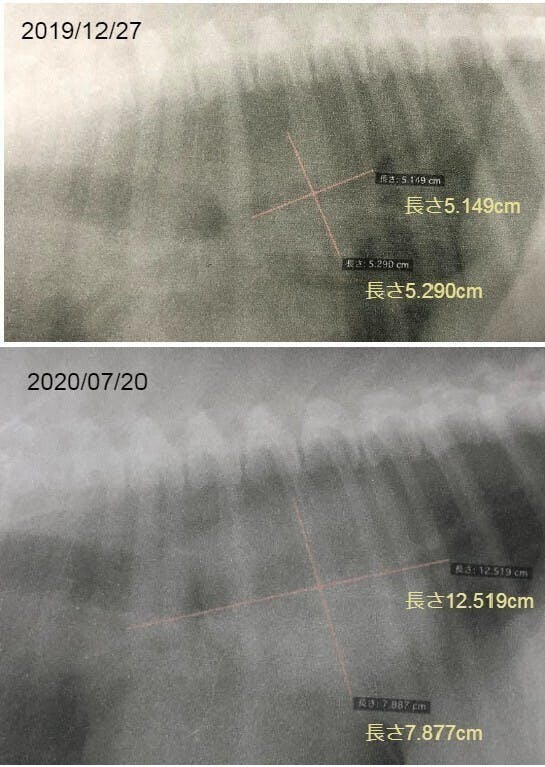

腫瘍が、7か月前に比べて2倍以上大きくなっていました。(泣)

これだけだとよくわからないと思うので、昨年末に撮ったレントゲン写真と並べてみました。

腫瘍の大きさが2倍以上になっていたのです(泣)